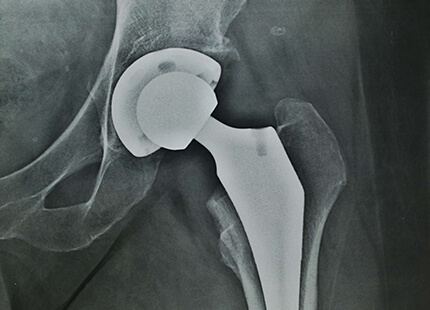

Заміна суглоба - операція не з простих, але сьогодні її роблять настільки часто, що для кваліфікованого лікаря в її проведенні немає нічого складного.

Ендопротезування кульшового суглоба (ціна є в прайсі) відновлює повністю функції нижніх кінцівок і дозволяє людині вільно, без дискомфорту пересуватися. Адже пошкодження тазостегнового суглоба призводить до того, що людина повністю перестає пересуватися через сильний біль.

Операція по заміні суглоба є абсолютно безпечною. При цій процедурі використовується високоякісний протез, який підбирається індивідуально під кожного пацієнта.